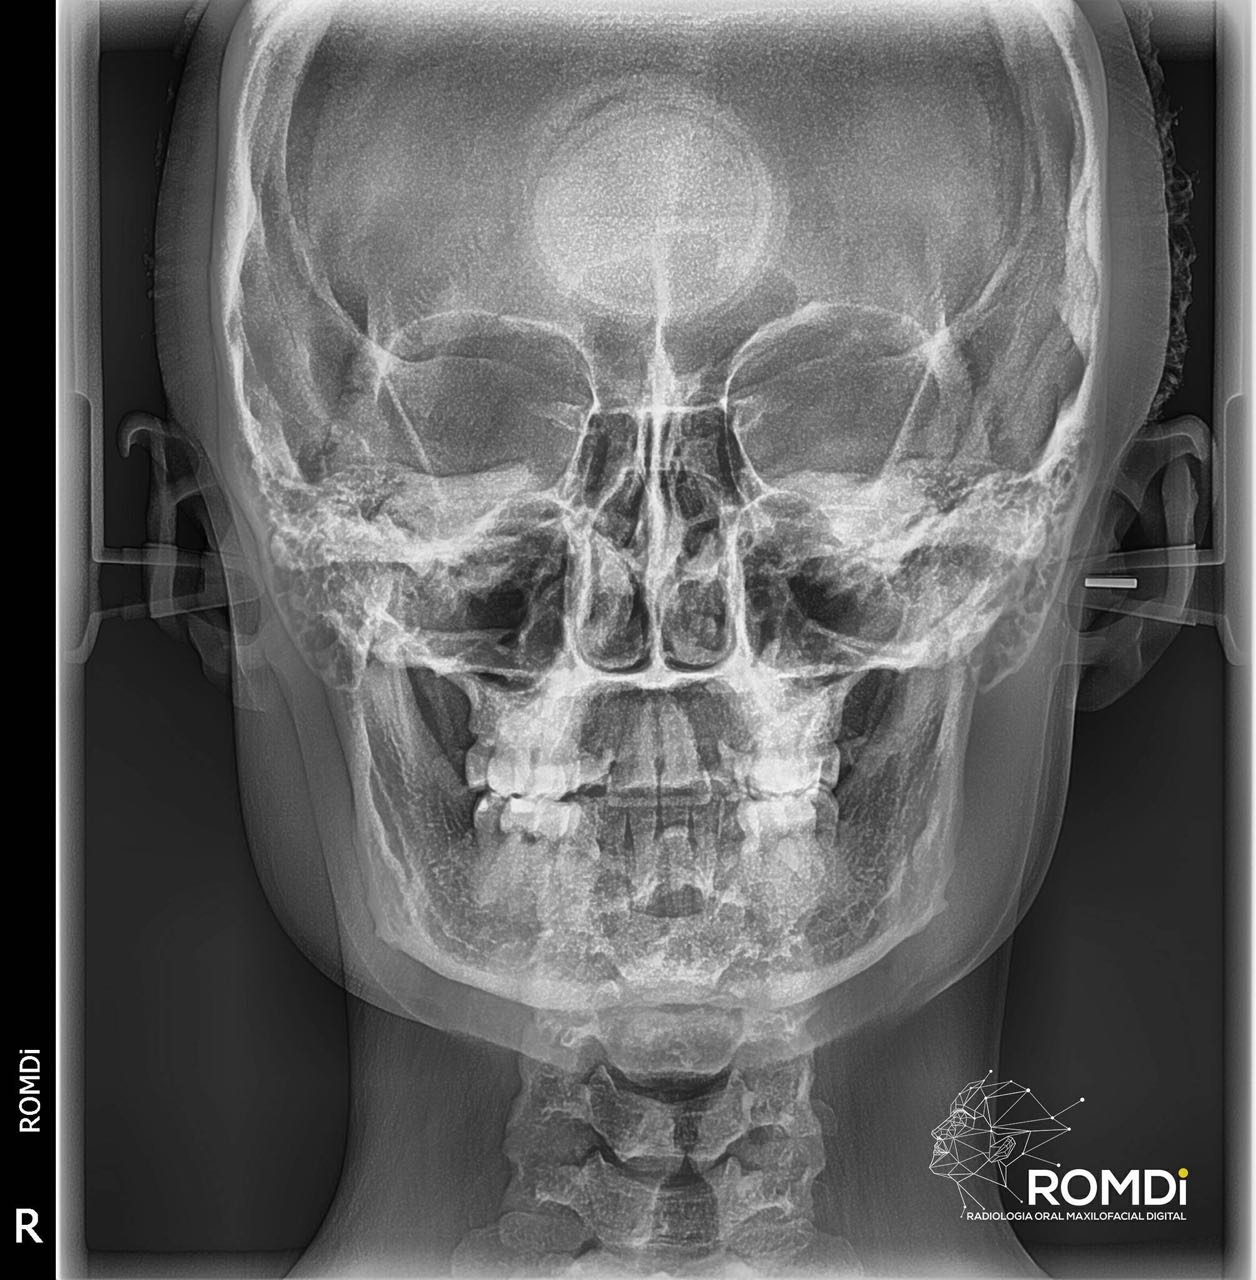

A través de la radiología, se conocen diferentes sistemas auxiliares de diagnóstico especializados de exploración, que nos proporcionan una información que ningún otro método nos puede ofrecer, tomando en consideración los avances técnico y científicos. En la materia de radiología, la actualización y aplicación de estos nuevos métodos, son necesarios para poder obtener el conocimiento básico y avanzado en el manejo de la interpretación radiográfica, así mismo, en conjunto con otros estudios clínicos, poder tener un diagnóstico acertado en las radiografías.

La radiografía panorámica permite la observación de ambos maxilares y la dentición, presentando una serie de relaciones únicas entre estas estructuras que no pueden ser encontradas en otro tipo de radiografías.